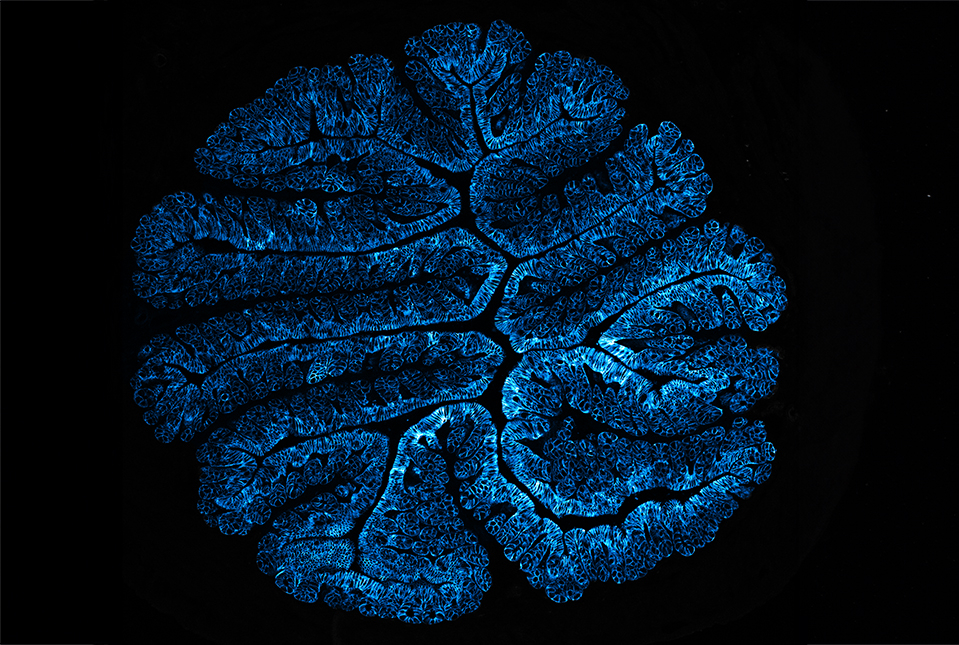

To get a better understanding of how the disease takes hold, Dr. Blander and her colleagues chose to study a mouse model of B-cell lymphoma called Eµ-myc, which has a mutation in the Myc oncogene. These mice have a long delay before tumors develop, giving researchers a chance to observe what happens early on in cancer. Because B-cell lymphoma develops in a type of white blood cell, the team examined their precursors, called hematopoietic stem cells, in the mice.